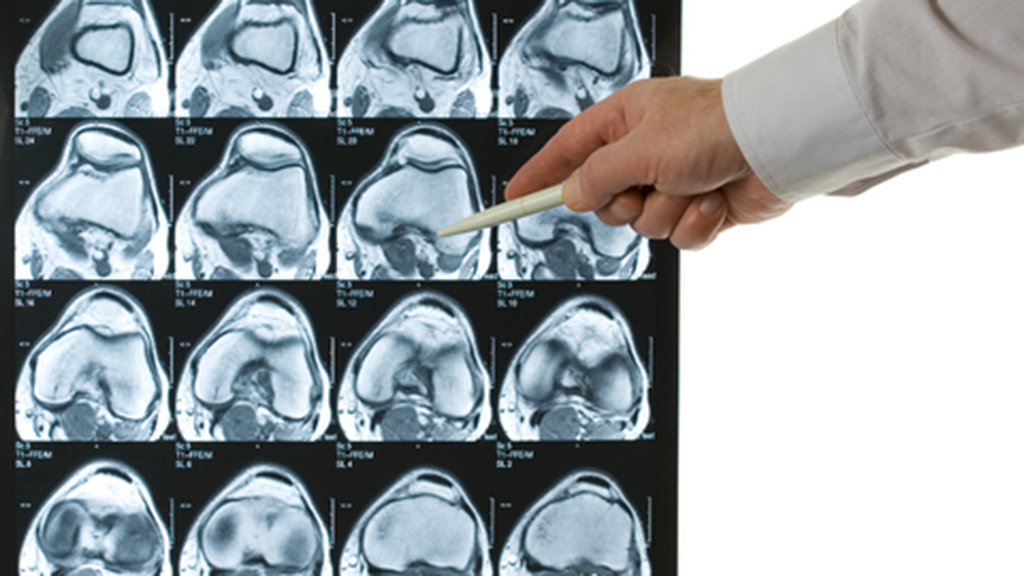

Based on a real incident, this case features an older woman who has been injured on a ski slope. Her classic knee injury, often referred to as the “Terrible Triad of O’Donahue,” is complicated by her age, the altitude, and possible hypothermia. In a stepwise fashion, students are introduced to the evaluation of the injury, structure of the knee joint, complicating factors, treatment of the injury, rehabilitation, and the patient’s eventual recovery. The topic of the case is often of particular interest to college-aged student-athletes, many of whom have faced a similar injury. Developed for students in the first semester of a two-semester anatomy and physiology course, the case could be adapted for a human biology course.